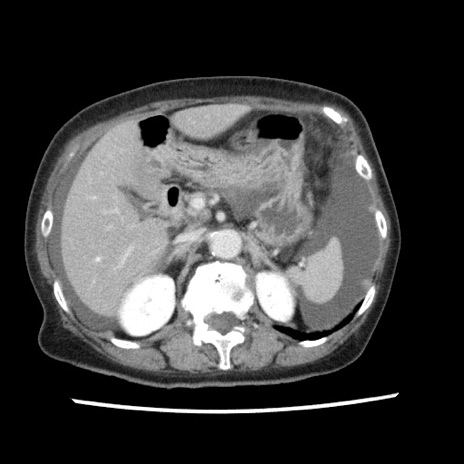

冠状断像

矢状断像